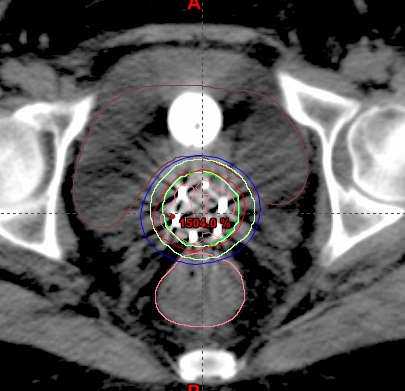

图3 医用直线加速器治疗头颈肿瘤病例